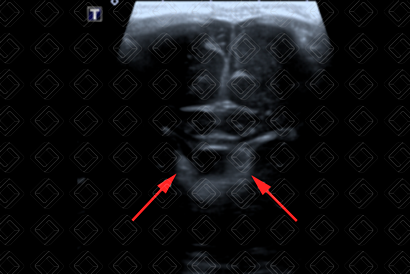

Texto alternativo para a imagem Figura 2. Créditos: Dra. Elazir Mota - Rio de Janeiro/RJ

Descrição das figuras 1 e 2: Ultrassonografia transfontanela; imagens coronal e parassagitais direita e esquerda evidenciando áreas triangulares hiperecogênicas (setas vermelhas) na topografia dos sulcos caudotalâmicos bilateralmente, compatível com hemorragia de matriz germinativa grau I bilateral.

A hemorragia de matriz germinal mais comumente inicia-se no sulco caudotalâmico, podendo estender-se para o interior dos ventrículos laterais, até mesmo para o parênquima cerebral.

• Grau I: Hemorragia presente somente no sulco caudotalâmico (figuras 1 e 2);